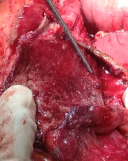

Εξερευνητική λαπαροτομία – Πολλαπλές διατρήσεις σε άλλο ασθενή με οζώδη πολυαρτηρίτιδα. Ευγενική παραχώρηση Dr. V. Penopoulos.